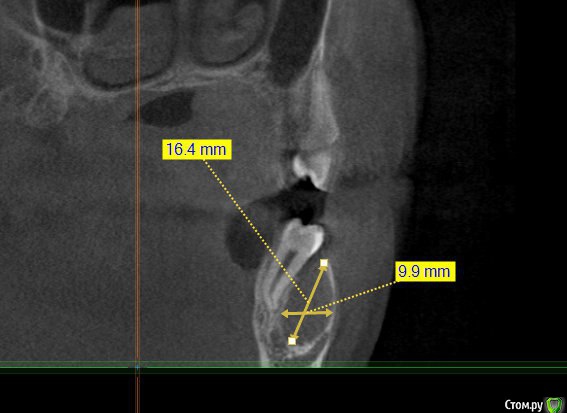

Kovalov Igor Опубликовано 14 июля, 2015 Поделиться Опубликовано 14 июля, 2015 (изменено) Уважаемые коллеги приветствую Вас! Встал вопрос стоит ли трогать фолликулярную кисту или наблюдать?Пациентка моя сестра, фолликулярная киста была случайной находкой, обнаружил ортодонт, отправил в областную больницу г. БелгородаВ детской ЧЛХ отказались, отправили в Харьков, это был 2013 год ещё. Во взрослой ЧЛХ не взялись, по возрасту. В детской члх сделали КТ, снимки и панораму прилагаю.Ps: картина за 2 года стала получше, но КТ сделают позже, есть внеротовой Rg снимок. Дело в том что я живу от сестры более 3000 км., сам бы это дело вскрыл амбулаторно, цистэктомия, графт+мембрана если гноя не будет... либо под йодоформом. Но вопрос стоит ли? и как по протоколу, каков Ваш план лечения? Депульпировать ли зубы 45-46? Изменено 14 июля, 2015 пользователем Kovalov Igor Ссылка на комментарий

Kovalov Igor Опубликовано 14 июля, 2015 Автор Поделиться Опубликовано 14 июля, 2015 вот Rg свежий. Вроде граница фолликулярной кисты уменьшилась.Как сделают КТ поделюсь тут... Буду признателен за ответы! Ссылка на комментарий